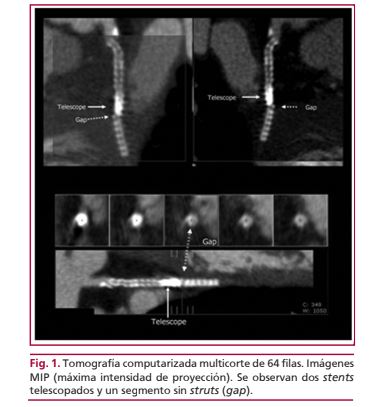

La fractura del stent es una complicación que se ha comunicado luego del implante de stents liberadores de sirolimus con una frecuencia que oscila entre el 1,9% y el 16% según las series y que se asocia con una tasa mayor de reestenosis y de eventos cardíacos a largo plazo. En esta presentación se describe el caso de un paciente en el que, casi 6 años después del implante de dos stents liberadores de sirolimus telescopados, a través de tomografia computarizada multidetector y angiografía invasiva se evidenció la fractura de los stents telescopados, asociada con oclusión del stent.